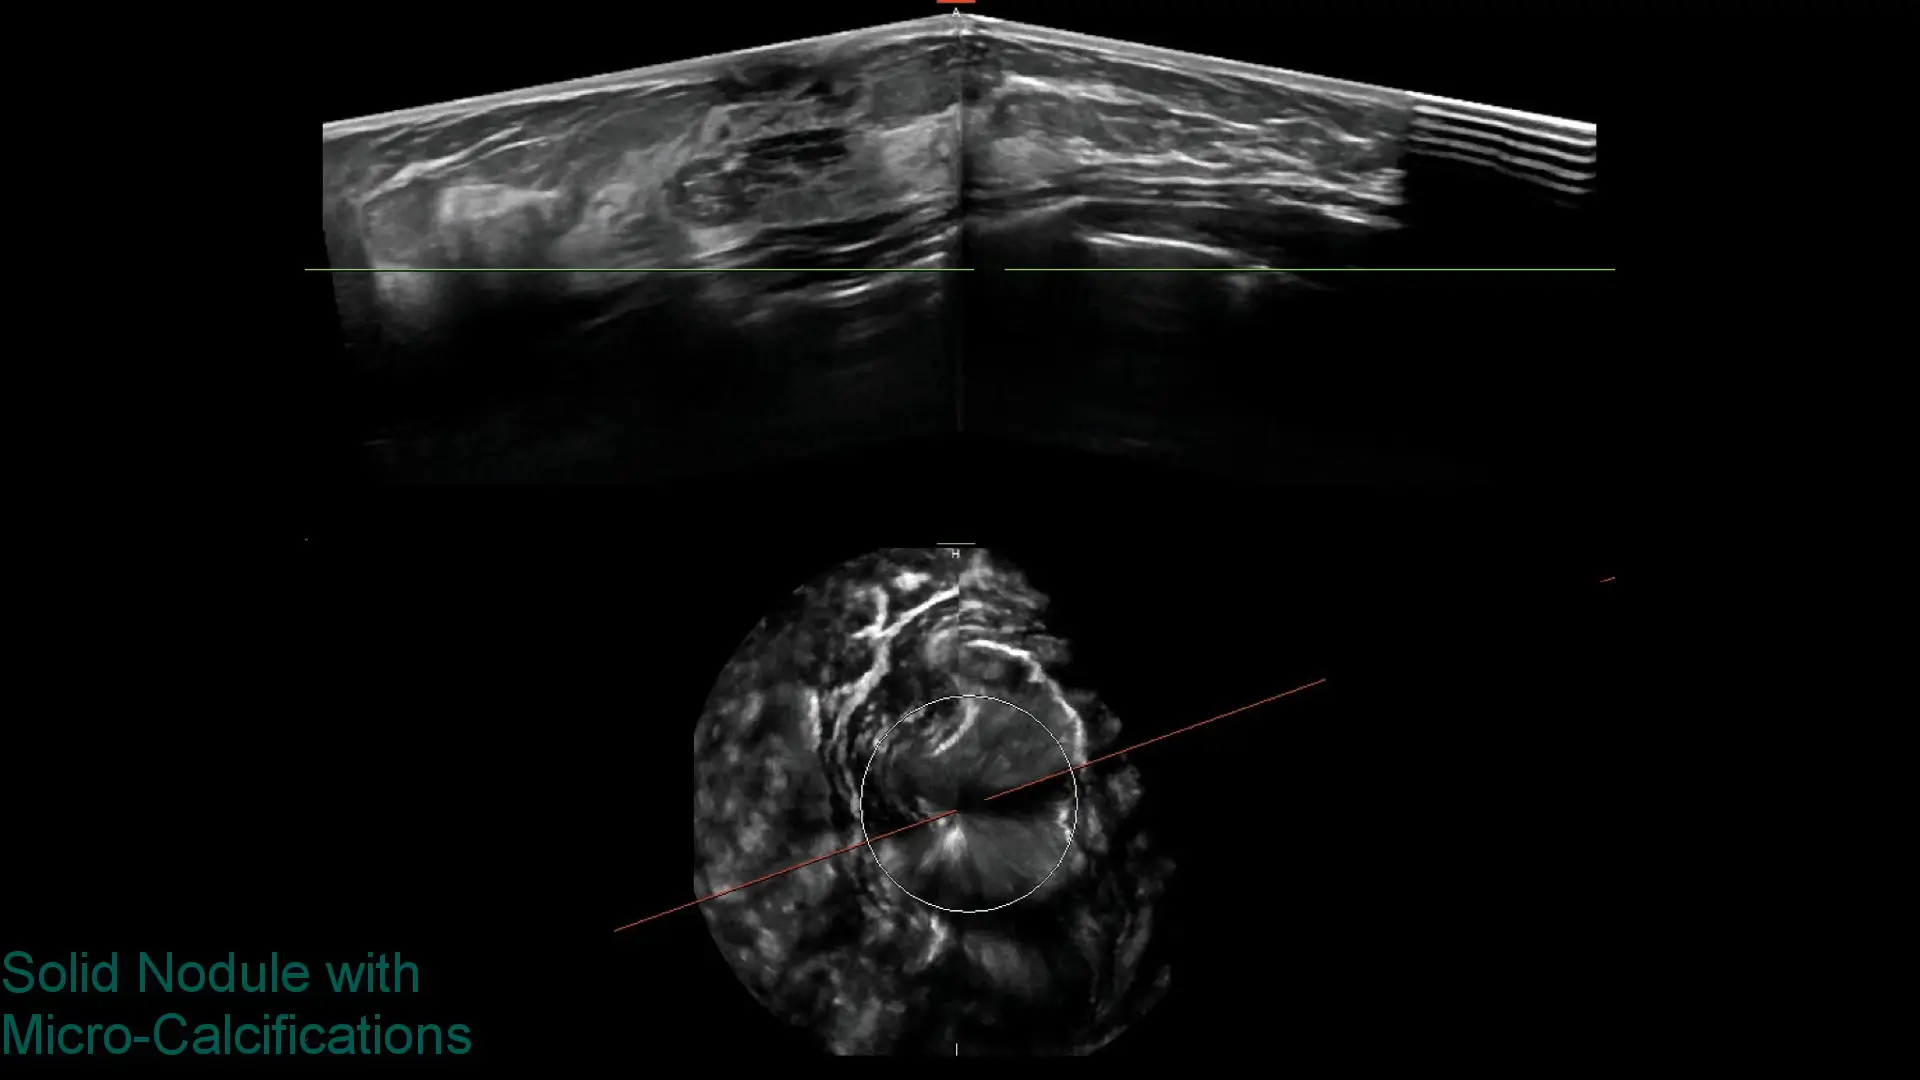

Explore clinical breast ultrasound images captured with SOFIA, showcasing various tissue types and conditions with exceptional clarity.